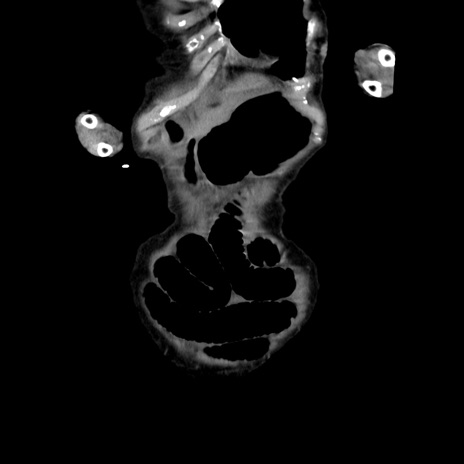

横断像

【症例】80歳代女性

【主訴】嘔吐、腹痛

【現病歴】数時間前より嘔吐あり。心窩部痛出現し、徐々に右下腹痛あり。その後も数回嘔吐あり救急搬送となる。

【身体所見】腹部は膨隆しているが軟らかく圧痛なし。腸雑音はやや亢進。

【データ】WBC 12000、CRP 19.05